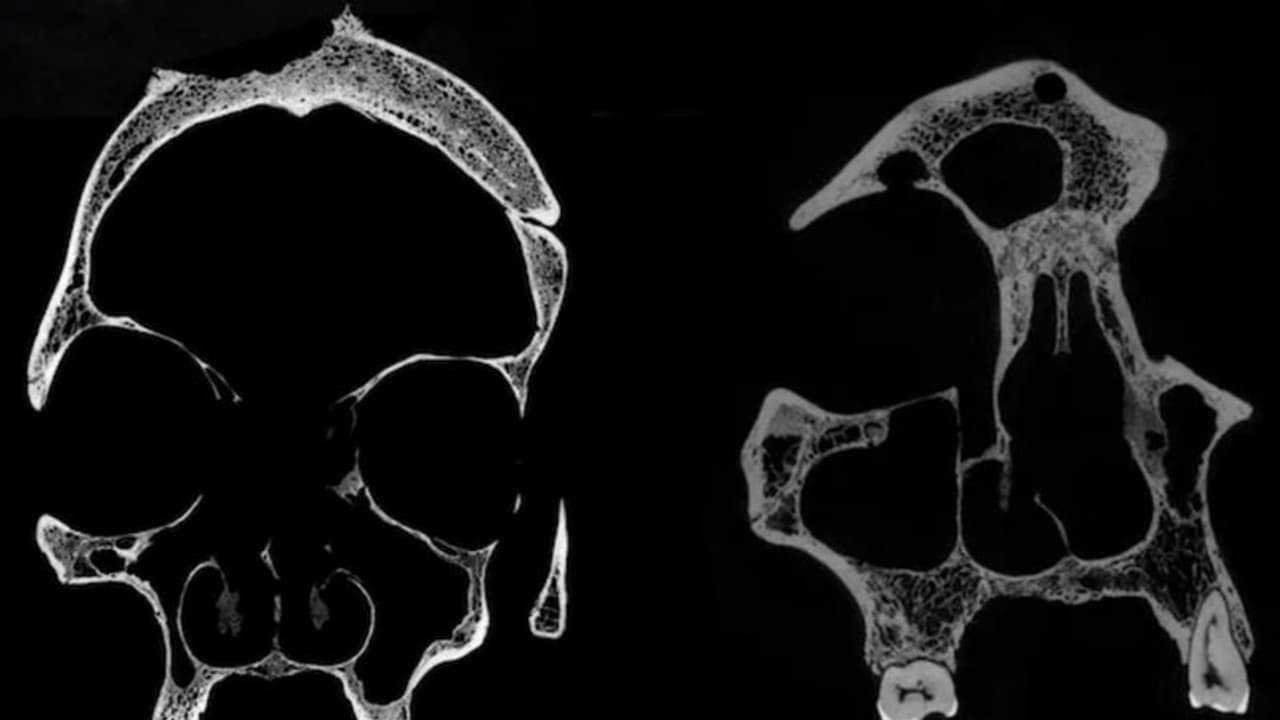

The two skulls, named Skull and Mandible 236, dating from between 2687 and 2345 BCE, belonged to a male individual aged 30 to 35, while Skull E270, dating from between 663 and 343 BCE, belonged to a female individual who was older than 50 years.

Upon microscopic examination, skull 236 exhibited a large-sized lesion consistent with excessive tissue destruction, identified as a neoplasm. Additionally, approximately 30 small and round metastasized lesions were scattered across the skull, accompanied by cut marks likely inflicted by a sharp object such as a metal instrument.

Examination of Skull E270 also revealed a significant lesion consistent with a cancerous tumor, resulting in bone destruction. Additionally, two lesions resulting from traumatic injuries were identified, indicating that they had undergone treatment.